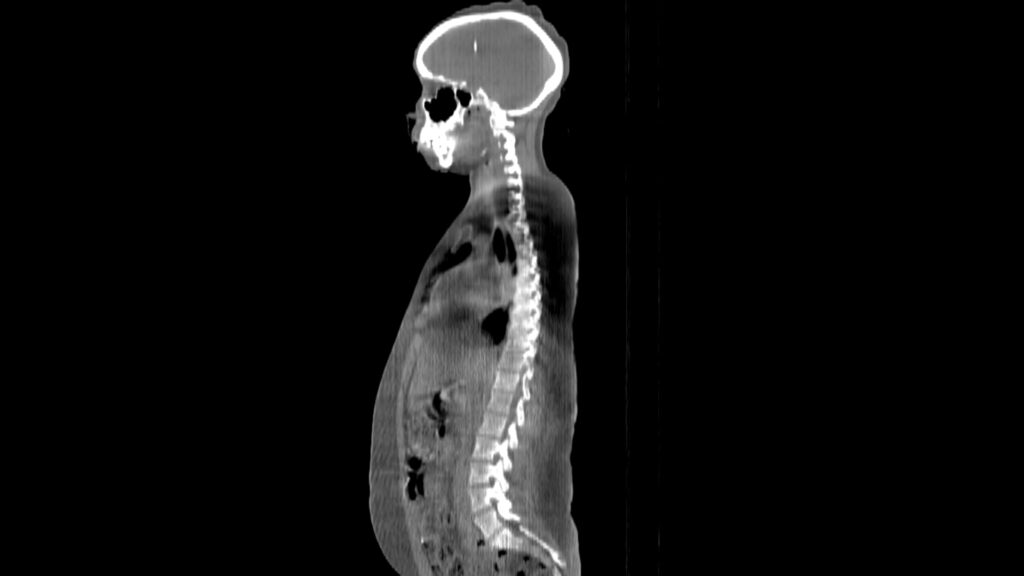

Planning CT Images

ClearRT® Images